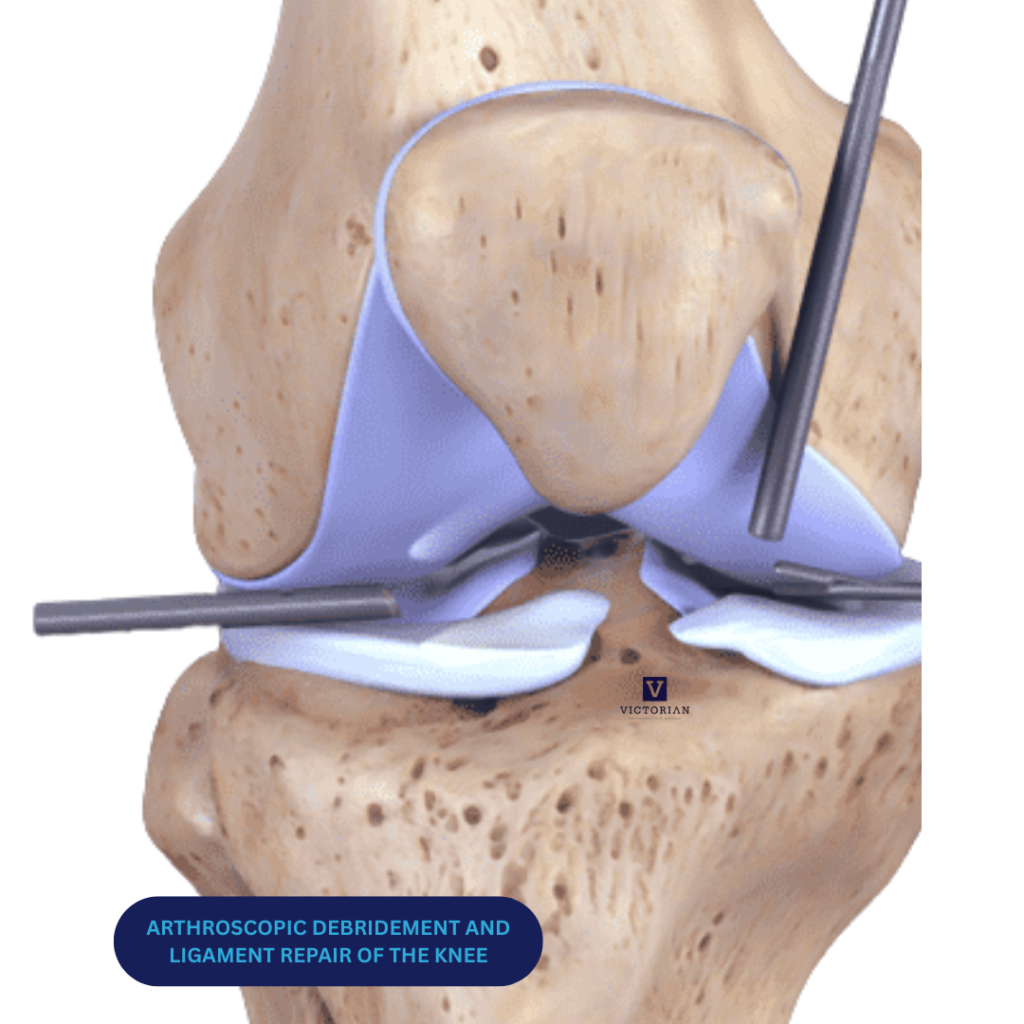

Arthroscopic Meniscal Repair

Arthroscopic Meniscal Debridement